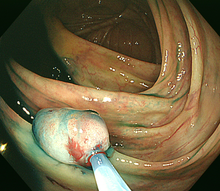

1)内視鏡的ポリープ切除術(ポリペクトミー)

大腸に隆起したポリープを認めた場合、ポリープの茎の部分に、内視鏡を通して通電ワイヤー(スネア)を掛け、ポリープを締め上げて高周波電流で切除します。高周波で切除することにより、切除した部位に熱凝固という作用が起きて止血できます。大腸粘膜には知覚神経がないため切除時には痛みは感じません。ポリープの大きさや形状によって1日から数日間の入院が必要です。